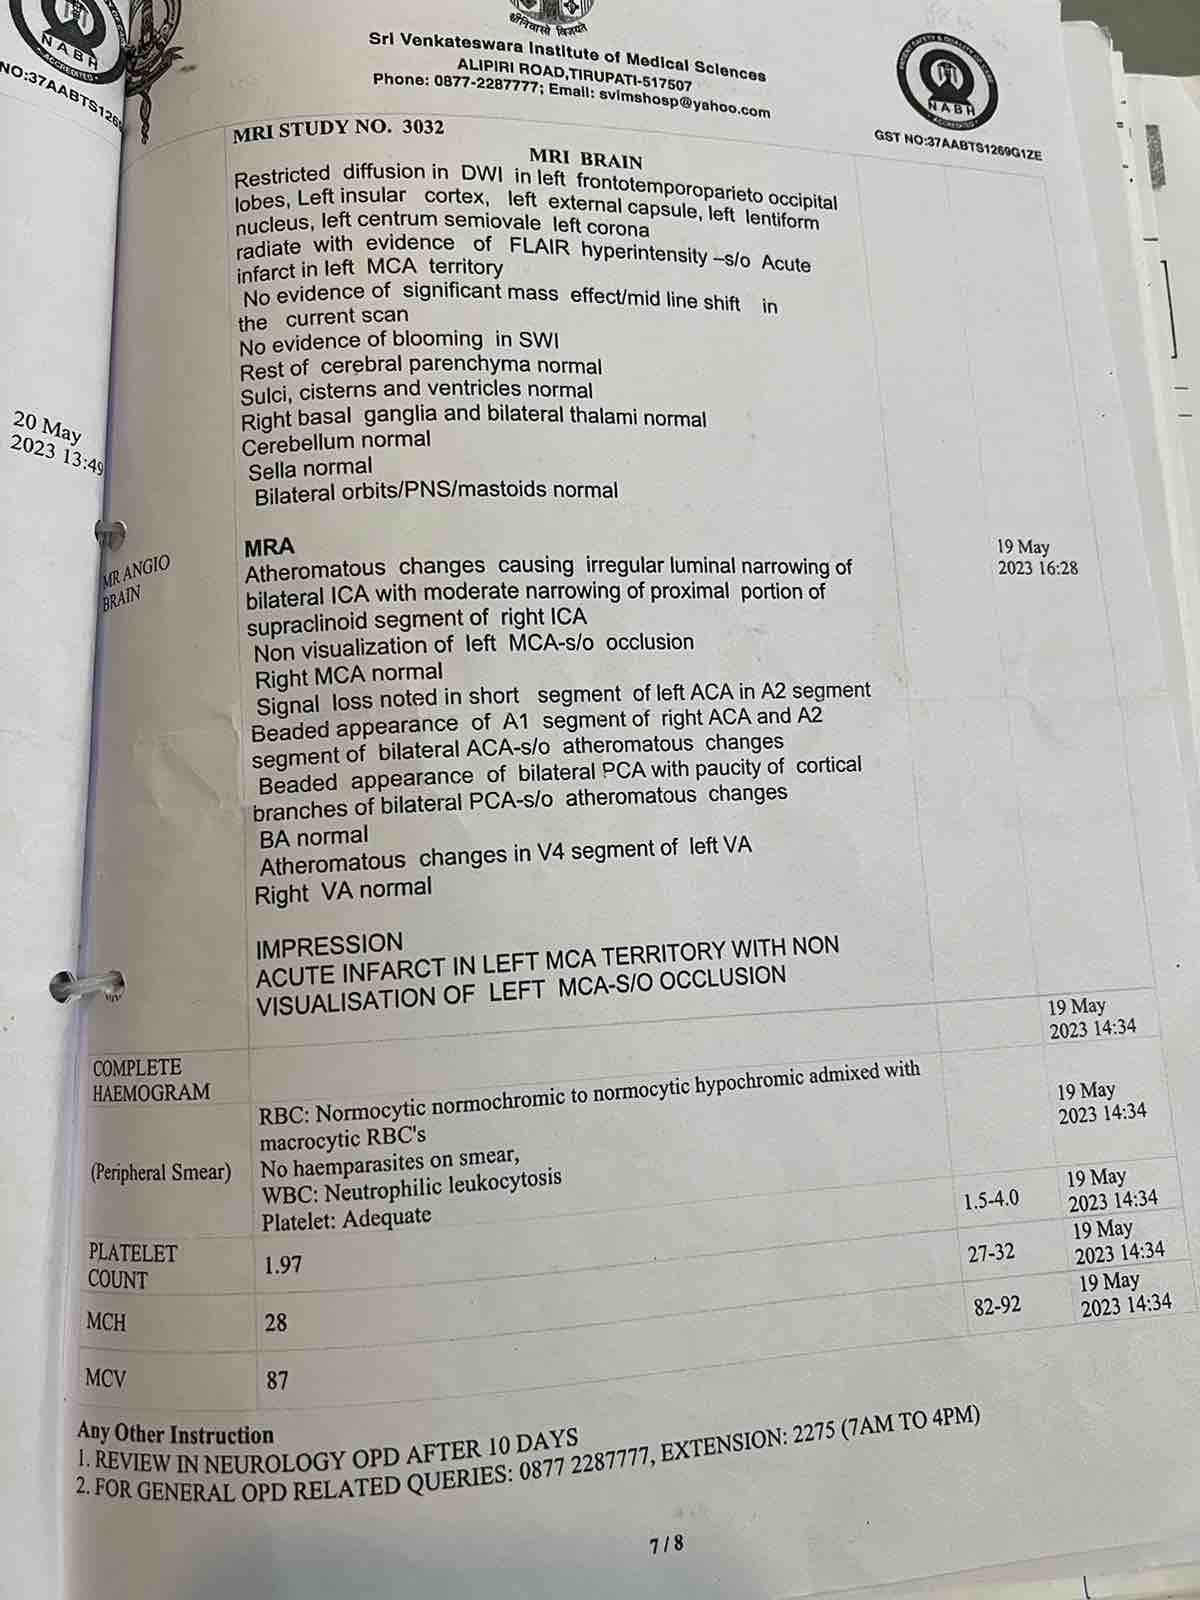

We are reaching out to you today with a heavy heart and a plea for help. Our beloved 66-year-old mother K VIJYA LAKSHMI, has been facing an incredibly challenging journey since 16th May when she had brain stroke & underwent emergency brain and abdomen surgery. Her recovery has been a rollercoaster of ups and downs.

During her hospitalization, she endured multiple complications, including respiratory distress, recurrent severe infections, and even seizure-like activity. Through it all, she has shown immense strength and determination. Still she require three more surgeries to stand on the path of recovery.